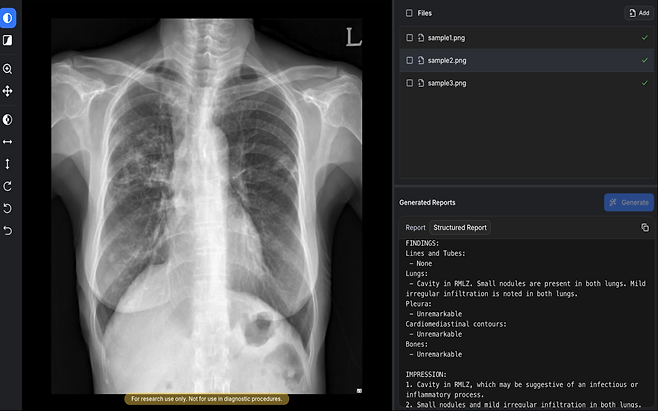

이 제품은 흉부 엑스레이 영상을 생성형 AI로 분석해 예비 소견서를 자동으로 생성하는 디지털 의료기기다. 흉수·기흉·폐부종·폐결절·심장비대 등 57종의 이상 소견을 분석해 텍스트 형태의 판독문 초안을 제공하고 영상 소견 해석까지 수행한다.

숨빗AI 기술의 핵심은 ‘판독문 초안 자동 생성’이다. 기존 AI 솔루션이 특정 병변을 표시하는 데 그쳤다면 이 제품은 영상 전체를 분석해 의료진이 작성하는 수준의 판독문 초안을 제시한다. 배 대표는 “기존에는 AI 결과를 참고해 의료진이 판독문을 다시 작성해야 했지만 이제는 초안을 기반으로 확인만 하면 된다”며 “판독 속도를 높이면서 정확도 개선도 기대할 수 있다”고 강조했다.